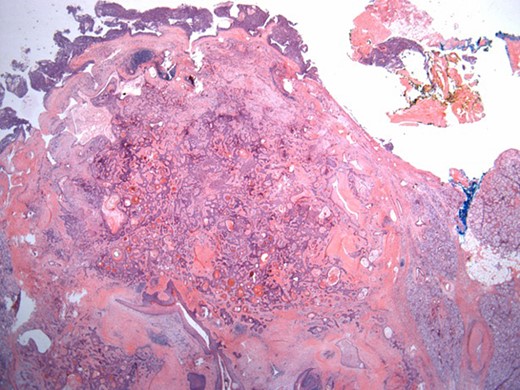

The surgical specimen showed a well-delineated submucosal nodule of 1.7 cm in the greatest diameter, without ulceration. Microscopically, this lesion appeared well defined with a central canal lined by keratinizing squamous epithelium without atypia (Fig. 2). In addition, we found confluent squamous foci with keratinizing centers (Fig. 3). The stroma was mostly fibrous, with occasional adipose and myxoid tissue. Only in the periphery of the lesion did we see a thin layer of normal ductal structures, highlighted by epithelial membrane antigen (EMA) positivity of the luminal cells, with immunochemistry studies (Fig. 4), whereas the other cellular component consisted of myoepithelial cells, highlighted by smooth muscle actin (SMA) and S100 protein (Fig. 5). No mucous secreting cell could be found. Keratin 5/6 and 903 were all positive for the whole specimen. The above-mentioned histopathologic findings helped to conclude the diagnosis of a PA with extensive squamous metaplasia. Margins were negative.

Well-circumscribed tumor on low power view. Hematoxylin and eosin (H&E ×25).

Solid sheets and massive squamous metaplasia with keratinization. Presence of adipose stroma. Hematoxylin and eosin (H&E ×40).